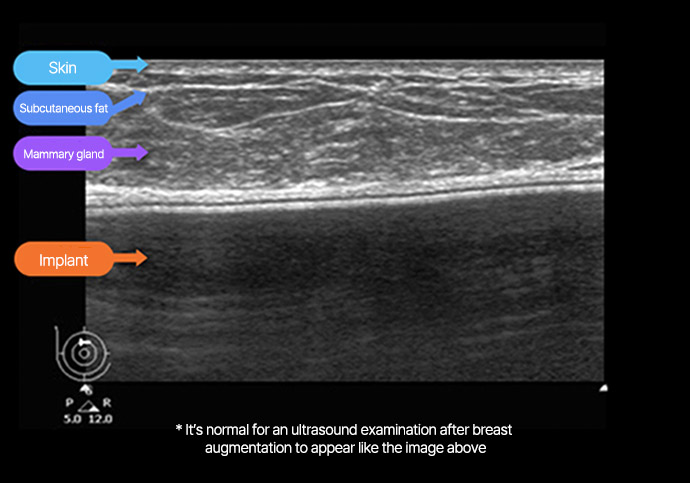

Precise diagnosis of breast health and implant

Status before and after surgery

* This is an actual breast ultrasound examination screen after

breast augmentation surgery at View Plastic Surgery. *